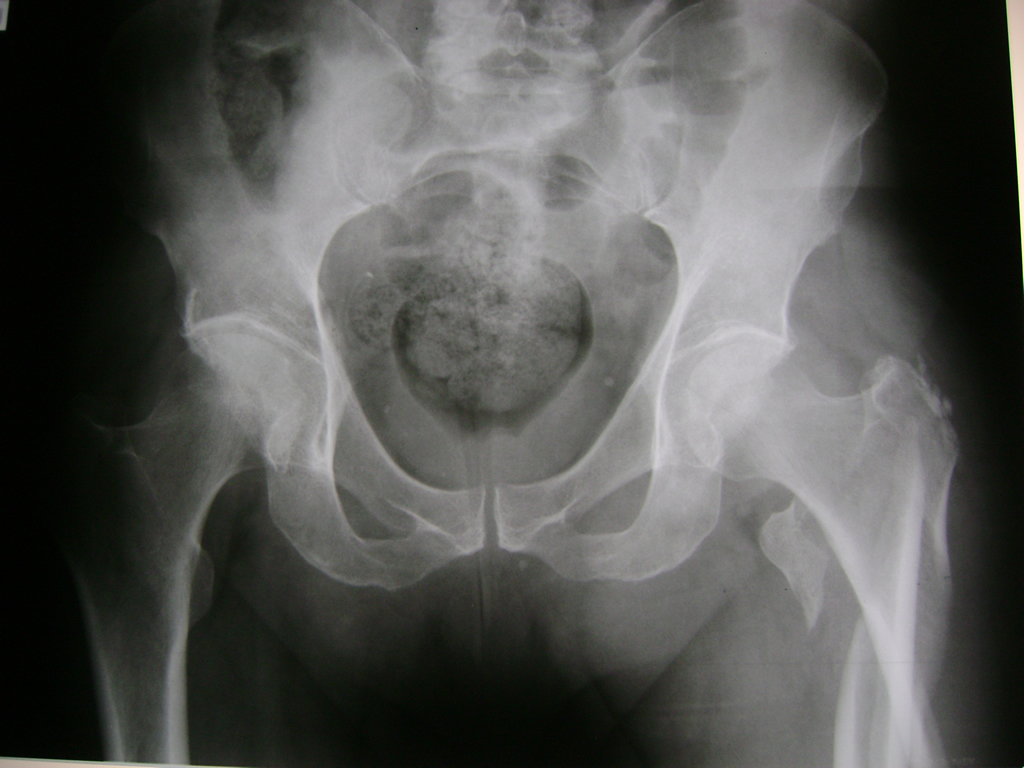

Cirugía de Fémur - Cadera

La cirugía de fractura de cadera se realiza para reparar una ruptura en la parte superior del hueso del muslo. Este hueso se denomina fémur.

Es parte de la articulación coxofemoral. Si una fractura de cadera no recibe tratamiento, es posible que deba permanecer en una silla o en la cama.